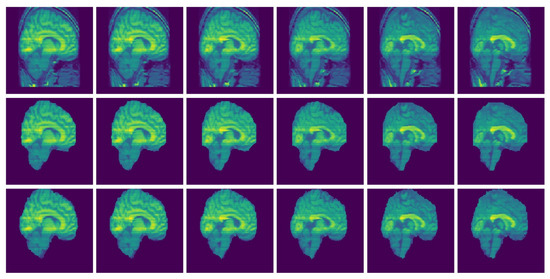

3. Results

Consistency Analysis of the GUBS across Different Data Sets